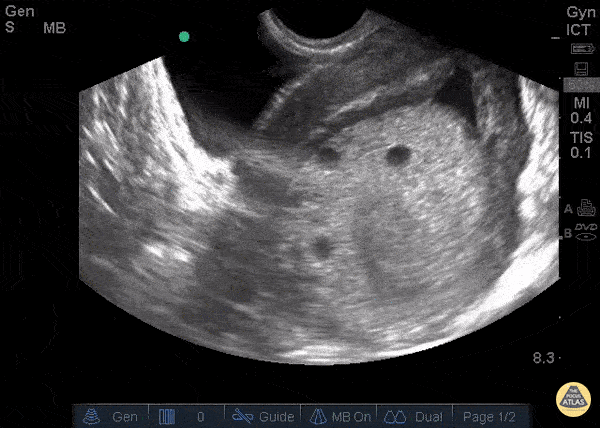

23 y/o F, gestational age 10 weeks by LMP referred to ER for suspicion of molar pregnancy. TV US shows hydropic vesicles within uterus, represented by anechoic regions scattered throughout a hyperechoic mass in uterine cavity. This is classically described as a “bunch of grapes” or “snowstorm pattern”. Patients diagnosed with molar pregnancy can present with vaginal bleeding or symptoms similar to hyperemesis gravidarum, making ER POCUS a useful evaluation tool that can expedite disposition. Dr. Bryan Flores, Dr. Teresa Smith - Kings County Emergency Medicine